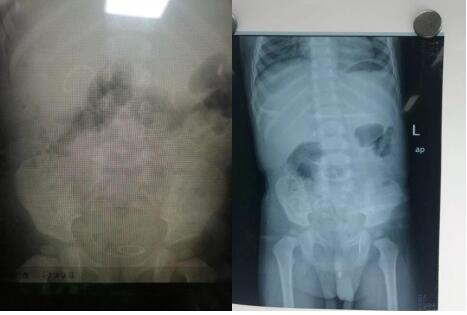

啄木鸟 泌尿外科成功为一岁半患儿实施 尿道结石钬激光碎石术